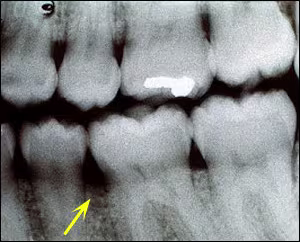

Bitewing Radiograph

A bitewing radiograph revealed slight bone loss at the crest of the alveolar bone between #19 and #20. (Figure 2) However, no obvious intrabony lesion was observed.

Figure 2. Bitewing radiograph showing only slight alveolar bone bone loss between #19 and #20.